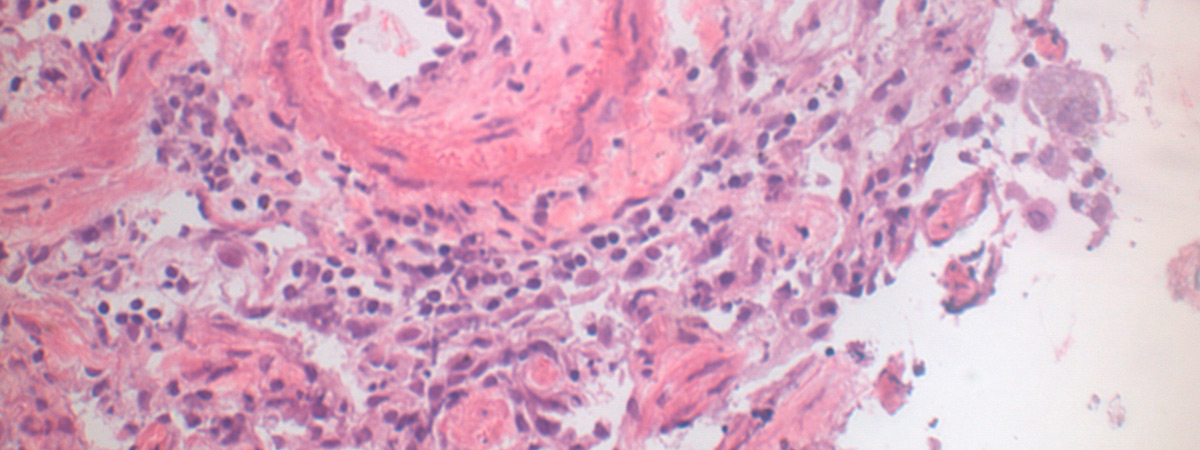

Idiopathic and heritable forms of pulmonary arterial hypertension (PAH) are devastating conditions associated with high morbidity and mortality. The disease is usually diagnosed late by finding a markedly increased pulmonary arterial pressure (increased blood pressure in the arteries of the lungs), the result of progressive narrowing and obliteration of the pulmonary vasculature, which often results in failure of the right ventricle. This disease tends to present in the middle decades of life, with a female predominance.

A major breakthrough in our understanding of the molecular basis of hypertension PAH was the identification of heterozygous germline mutations in the bone morphogenetic protein type II receptor (BMPR-II) in the majority (>70%) of familial cases of the disease and a significant proportion (15-26%) of sporadic cases. Although the presence of mutations in BMPR-II is the greatest risk factor for the development of PAH, it is estimated that only 20% of carriers develop the disease. Additional factors are required for disease manifestation. These may be genetic and/or environmental, though the identity of these factors remains unknown.